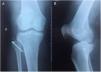

Presentación del casoSe trata de una paciente de sexo femenino de 65 años, obesa, que sufre una caída desde su propia altura, produciendo trauma directo a nivel lateral de la rodilla derecha en flexión. Es llevada al servicio de emergencia por presentar dolor de la rodilla derecha que se incrementa al ponerse de pie y al realizar movimientos activos de rodilla. Al examen físico; IMC 30, álgica, se evidencia equimosis en zona lateral de la rodilla derecha, se realiza pruebas de estabilidad encontrándose bostezo lateral positivo. Neurovascular (sensibilidad), tono fuerza muscular de la cara externa y dorsiflexión del pie conservado. El estudio de imagen reveló fractura-avulsión de la cabeza de fíbula derecha. Debido a la lesión del ligamento colateral se decidió tratamiento quirúrgico, reducción abierta más osteosíntesis con tornillo y refuerzo de ligamento colateral lateral (LCL) con sutura transósea. Consiguiendo estabilidad adecuada de la rodilla (figs. 1 y 2).

Estudios revelan que en Rx incluso pueden pasar desapercibidas como también en casos de luxaciones tibiofibulares proximal. La Rx que se realizó más el examen físico fue suficiente para un diagnóstico y tratamiento específico adecuado8.